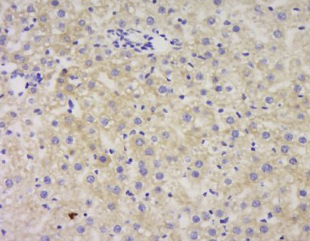

组织/细胞:小鼠肝组织,4%多聚甲醛固定、石蜡包埋;

抗原检索:柠檬酸缓冲液(0.01M,pH 6.0),沸水浴15min;座城市和过氧化物酶3 %过氧化氢30min;阻塞缓冲(正常山羊血清C - 0005)37℃20分钟;

孵化:抗α1-抗糜蛋白酶polyclonal抗体,unconjugated(BS 0094r)1∶200,隔夜以4°C,随后两个中等城市conjugation抗体(P 0.023)和(C 0010 DAB)染色